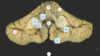

Which structure is the arrow pointing? Thalamus Global pallidus Internal capsule Caudate nucleus Putamen

Which structure is the arrow pointing? Thalamus **Global pallidus** Internal capsule Caudate nucleus Putamen

40

Which structure is the arrow pointing? **Thalamus** Global pallidus Internal capsule Caudate nucleus Putamen